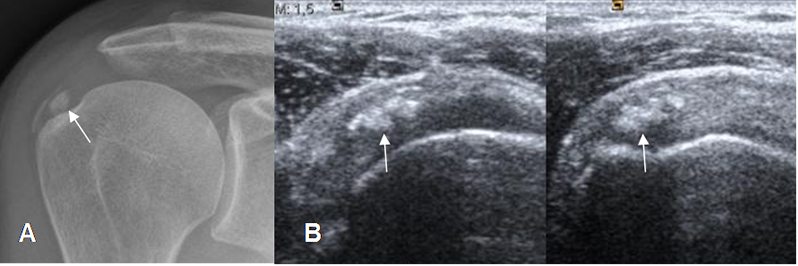

Fig 128. Tendinitis del supraespinoso.

A y B: Ecografía coronal. Cambios inflamatorios del supraespinoso, con líquido en la superficie bursal en A y sobre la superficie humeral en B.